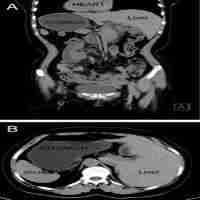

| Abstract | Background Despite increasing acceptance in colorectal surgery, natural orifice specimen extraction (NOSE) surgery for the treatment of gastric cancer is still in its infancy, especially via the transrectal approach, which was barely reported. So little is known about its complications. Here we report the first case of proctotomy leak after transrectal NOSE gastrectomy, and our experience in preventive interventions. Case presentation A 62-year-old male patient complaining of upper abdominal pain who underwent open distal gastrectomy for gastric cancer one year ago was diagnosed with recurrent gastric cancer by gastroscopic biopsy. We performed laparoscopic total gastrectomy with transrectal specimen extraction on the patient. The operation was completed in a total laparoscopic approach and the specimen was extracted through a 3 cm longitudinal incision in the anterior wall of the upper rectum, then interrupted sutures were used for full-thickness closure of the rectal incision. The operative time was 470 min and intra-operative blood loss was 100 mL. The postoperative pathological examination showed pT1bN0M0 gastric adenocarcinoma. The patient developed proctotomy leak on the 10th postoperative day. We analyzed the causes of this rare complication and put forward a series of technical improvements. After failure of conservative treatment, a diverting ileostomy was created and the patient eventually recovered. We successfully prevented proctotomy leak in the subsequent 20 transrectal NOSE gastrectomies using improved techniques. Conclusions Proctotomy leak after transrectal specimen extraction should be considered among the complications of NOSE surgery and can be prevented by technical precautions. |